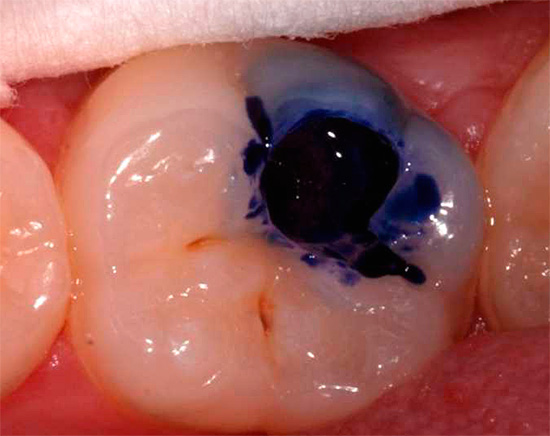

Meno comunemente, il blu di metilene viene utilizzato per rilevare la carie, che funziona in modo simile alla fucsina, ma colora di blu le aree interessate.